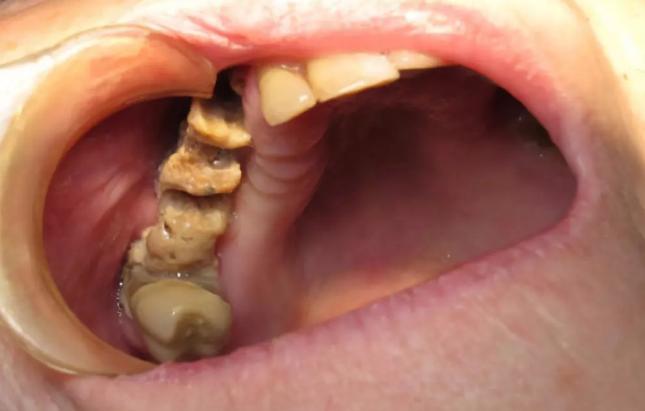

牙 双膦酸盐相关性颌骨坏死(BRONJ)作为使用BPs药物引起的严重不良反应,由口腔科医生Marx2003年首次报道。。根据2009年美国口腔颌面外科医师协会(AAOMS)确立的BRONJ诊断标准,可定义BRONJ为:口腔颌面部存在8周未愈合的骨面暴露,且患者正在接受或接受过BPs药物治疗但无头颈部放疗史。该病发病率虽低,但由于严重的临床表现,并且尚无有效根治方法,近年来受到越来越多学者的关注。(图4)

牙 双膦酸盐相关性颌骨坏死的发病机制较复杂,目前学者通过研究提出了数种假说。其中较受关注的是,口腔外科操作导致颌骨创伤后,双膦酸盐通过抑制破骨细胞活性,抑制颌骨表面溶骨性活动,诱导破骨细胞凋亡,间接抑制成骨细胞的骨质沉积作用,使骨重建速度减慢,增加下颌骨坏死风险。值得注意的是,根据现有的文献报道,BRONJ只发生在颌骨,尚未发生在其他骨。(图5 6)

牙 BRONJ的临床表现与放射性颌骨坏死类似,患者可能长期无明显症状,也可表现为颌骨疼痛或骨面裸露。典型的临床表现包括疼痛、骨面裸露、软组织肿胀、感染、牙齿松动、溢脓、瘘管形成。也可见骨面暴露但不伴感染症状的病例。其他症状还包括牙关紧闭、口臭、复发性脓肿、上颌窦炎、口腔上颌窦瘘等。当压迫周围神经时,可出现剧烈的颌骨疼痛或麻木,病情严重者甚至出现病理性骨折。